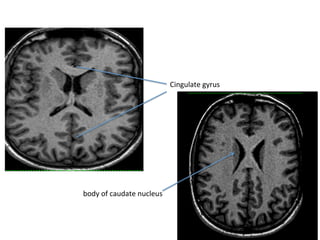

Cingulate	gyrus

body	of	caudate	nucleus